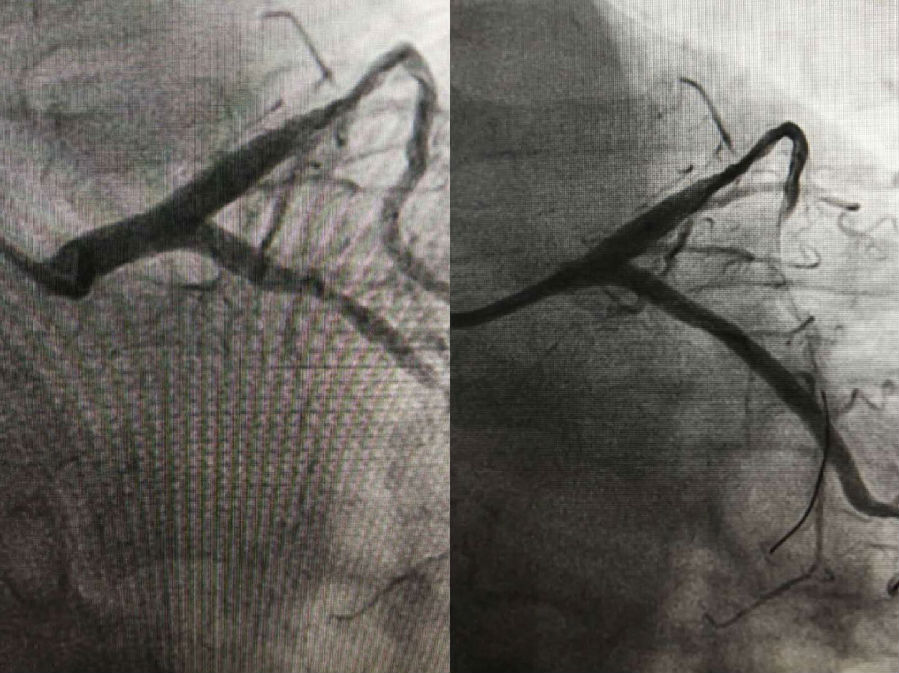

2017年12月17日,在北京阜外醫(yī)院心內(nèi)科冠脈介入中心張洪亮教授的指導(dǎo)下,我院成功為四位冠心病患者實(shí)施了冠狀動(dòng)脈介入治療術(shù)。

手術(shù)由我院心內(nèi)科侯濤主持,趙丁峰操作治療,放射科趙貴生主任和王海申副主任配合,呂懷智副院長(zhǎng)和心內(nèi)科陳彥主任全程監(jiān)控,為其中三位患者成功進(jìn)行了支架植入術(shù)和一例冠狀動(dòng)脈造影術(shù),目前患者均恢復(fù)良好,實(shí)現(xiàn)了不出遠(yuǎn)門(mén),即可在我院接受治療

冠狀動(dòng)脈造影術(shù)是通過(guò)穿刺血管,對(duì)冠狀動(dòng)脈狹窄或閉塞部位進(jìn)行治療,使血管管腔恢復(fù),從而達(dá)到血運(yùn)重建、恢復(fù)心肌供血。此類(lèi)手術(shù)的成功開(kāi)展,對(duì)今后冠狀動(dòng)脈粥樣硬化性心臟病手術(shù)治療的全面開(kāi)展起到了積極的推動(dòng)作用,這也是我院為滿(mǎn)足人民群眾健康需求和促進(jìn)衛(wèi)生事業(yè)更進(jìn)一步發(fā)展,更好地為廣大患者服務(wù)的又一碩果。